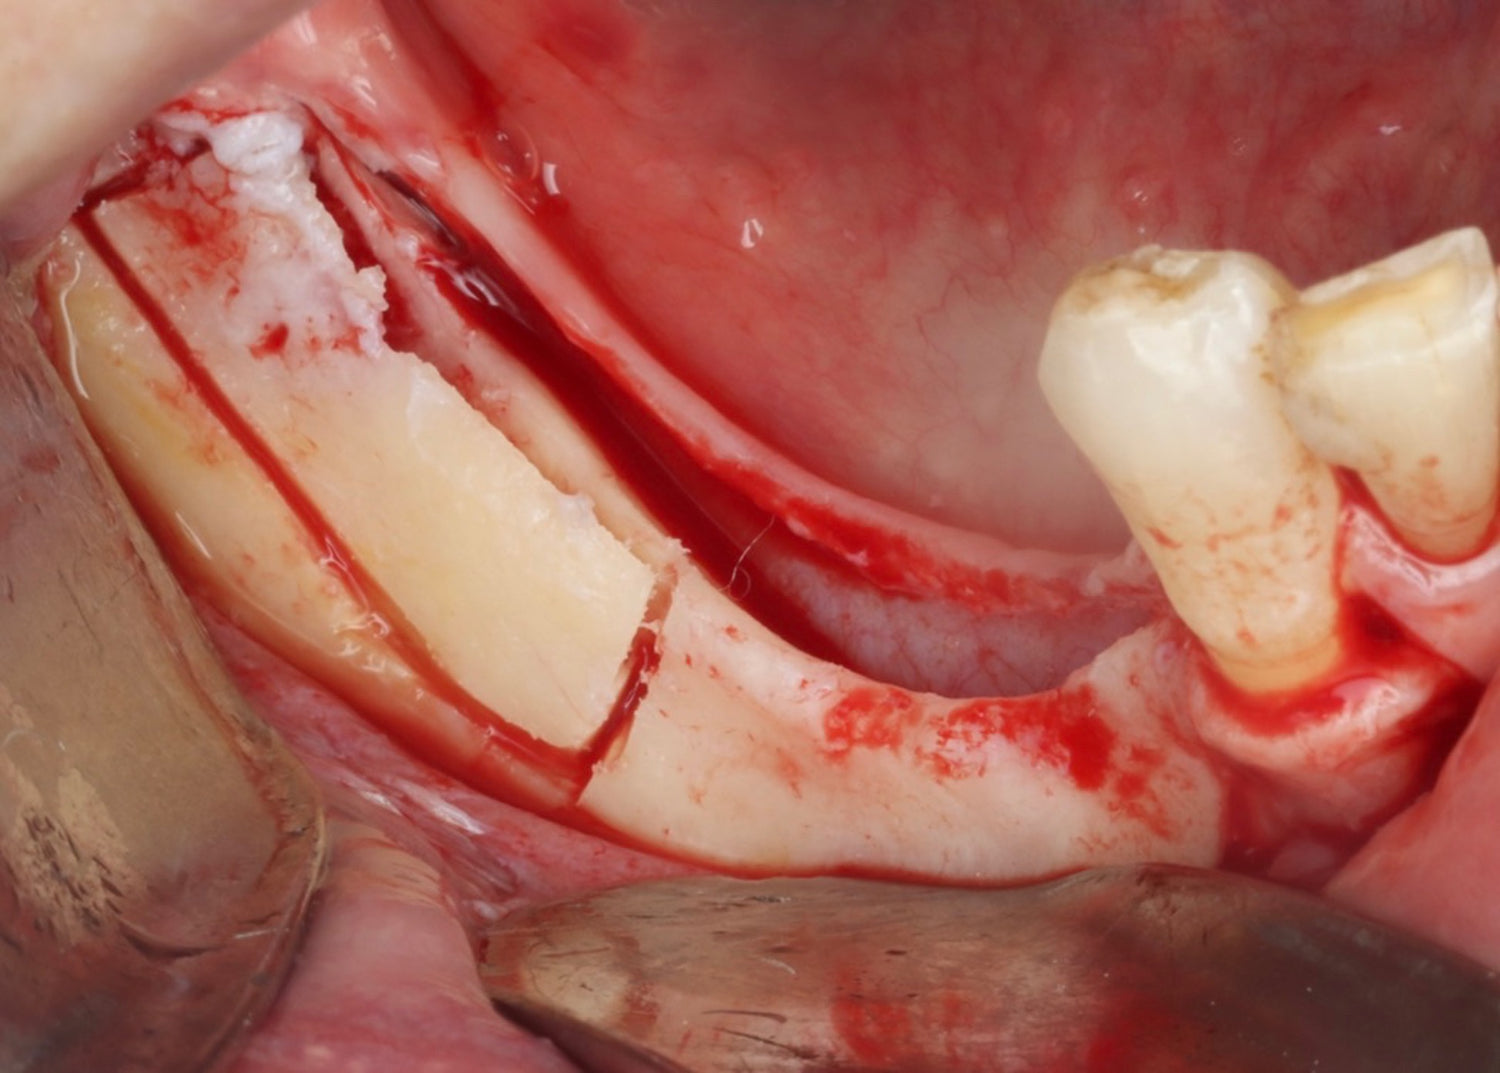

- Ridge splitting

- Khoury plate